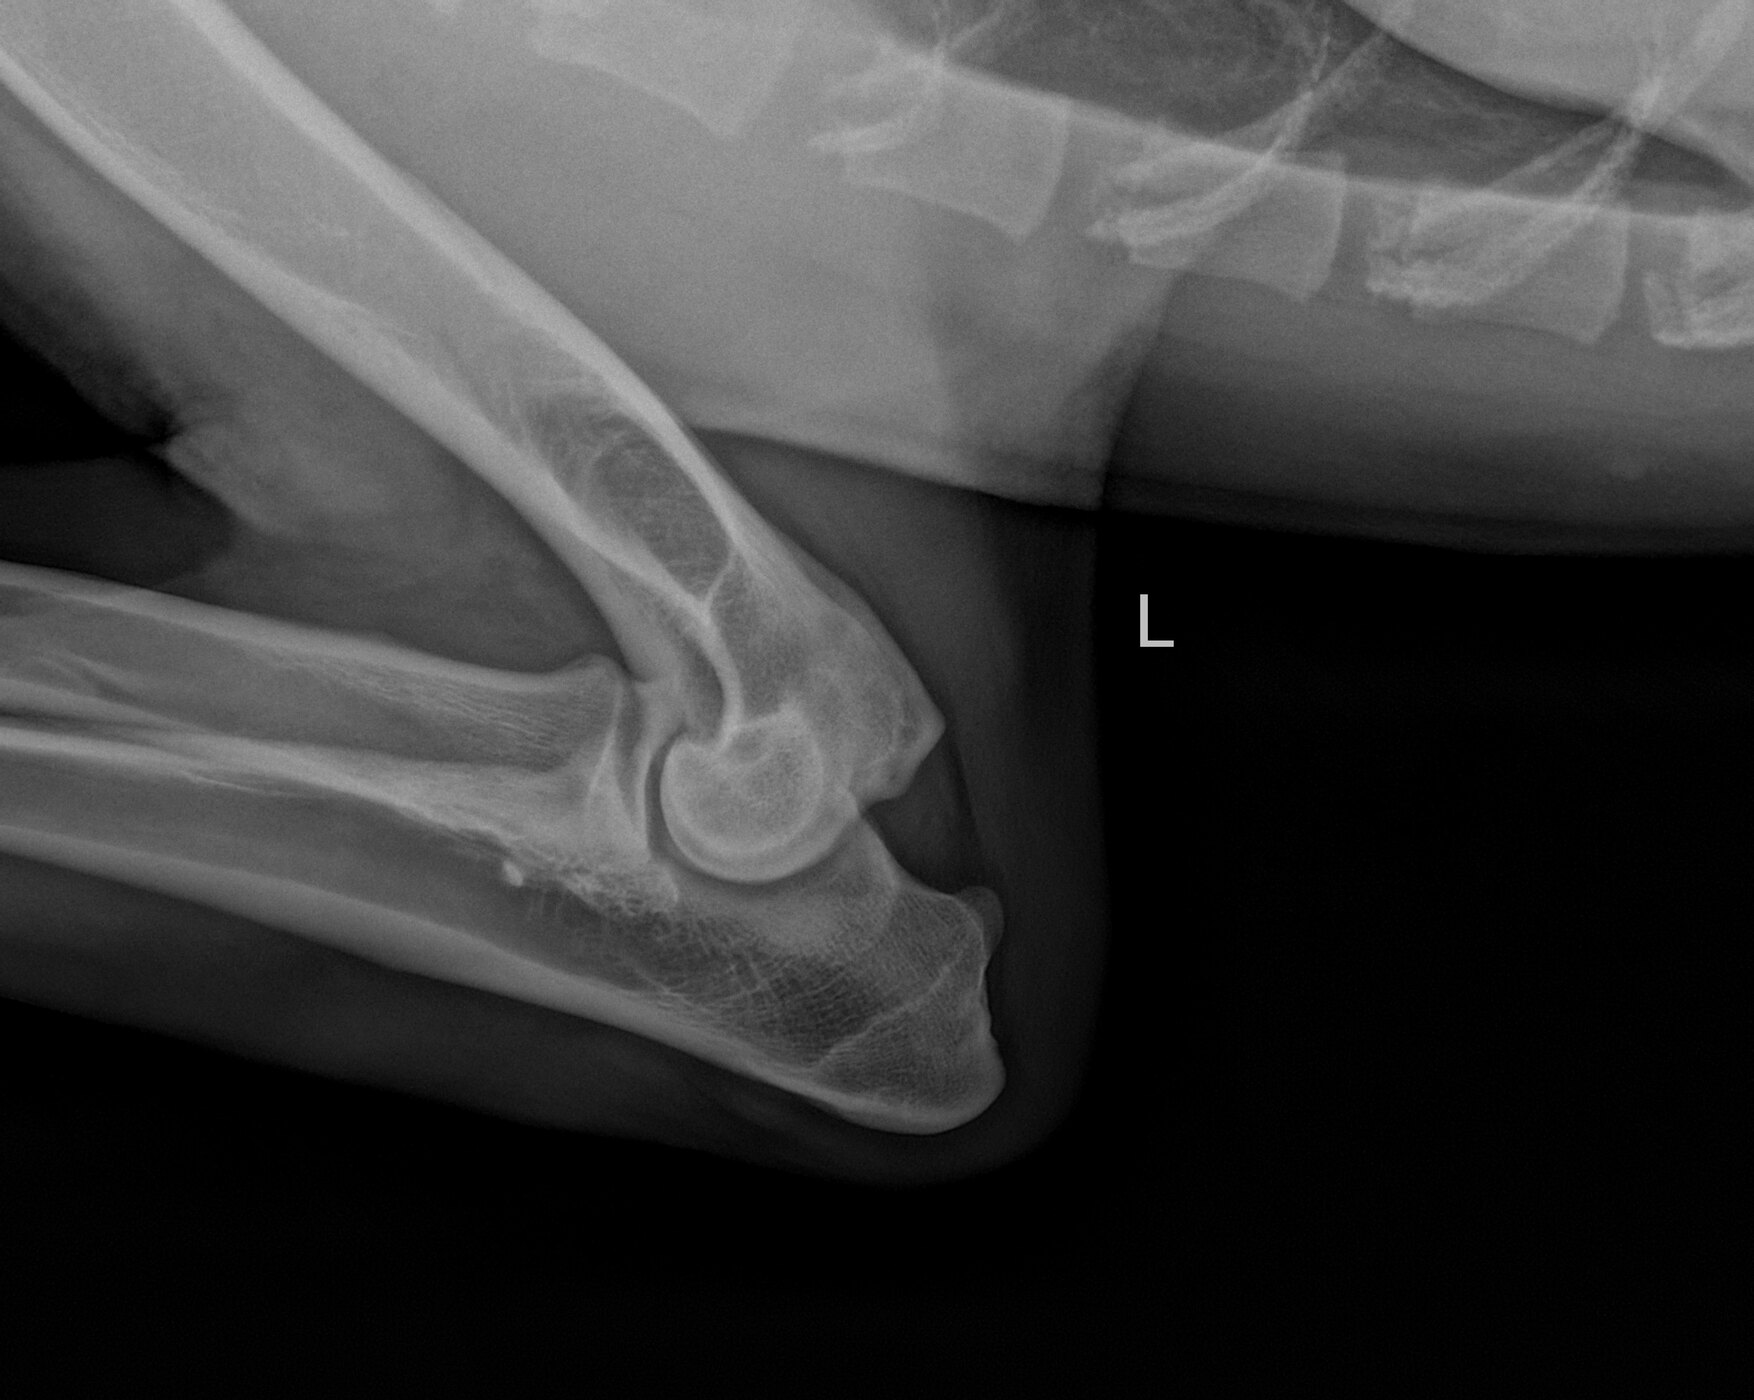

Bentley